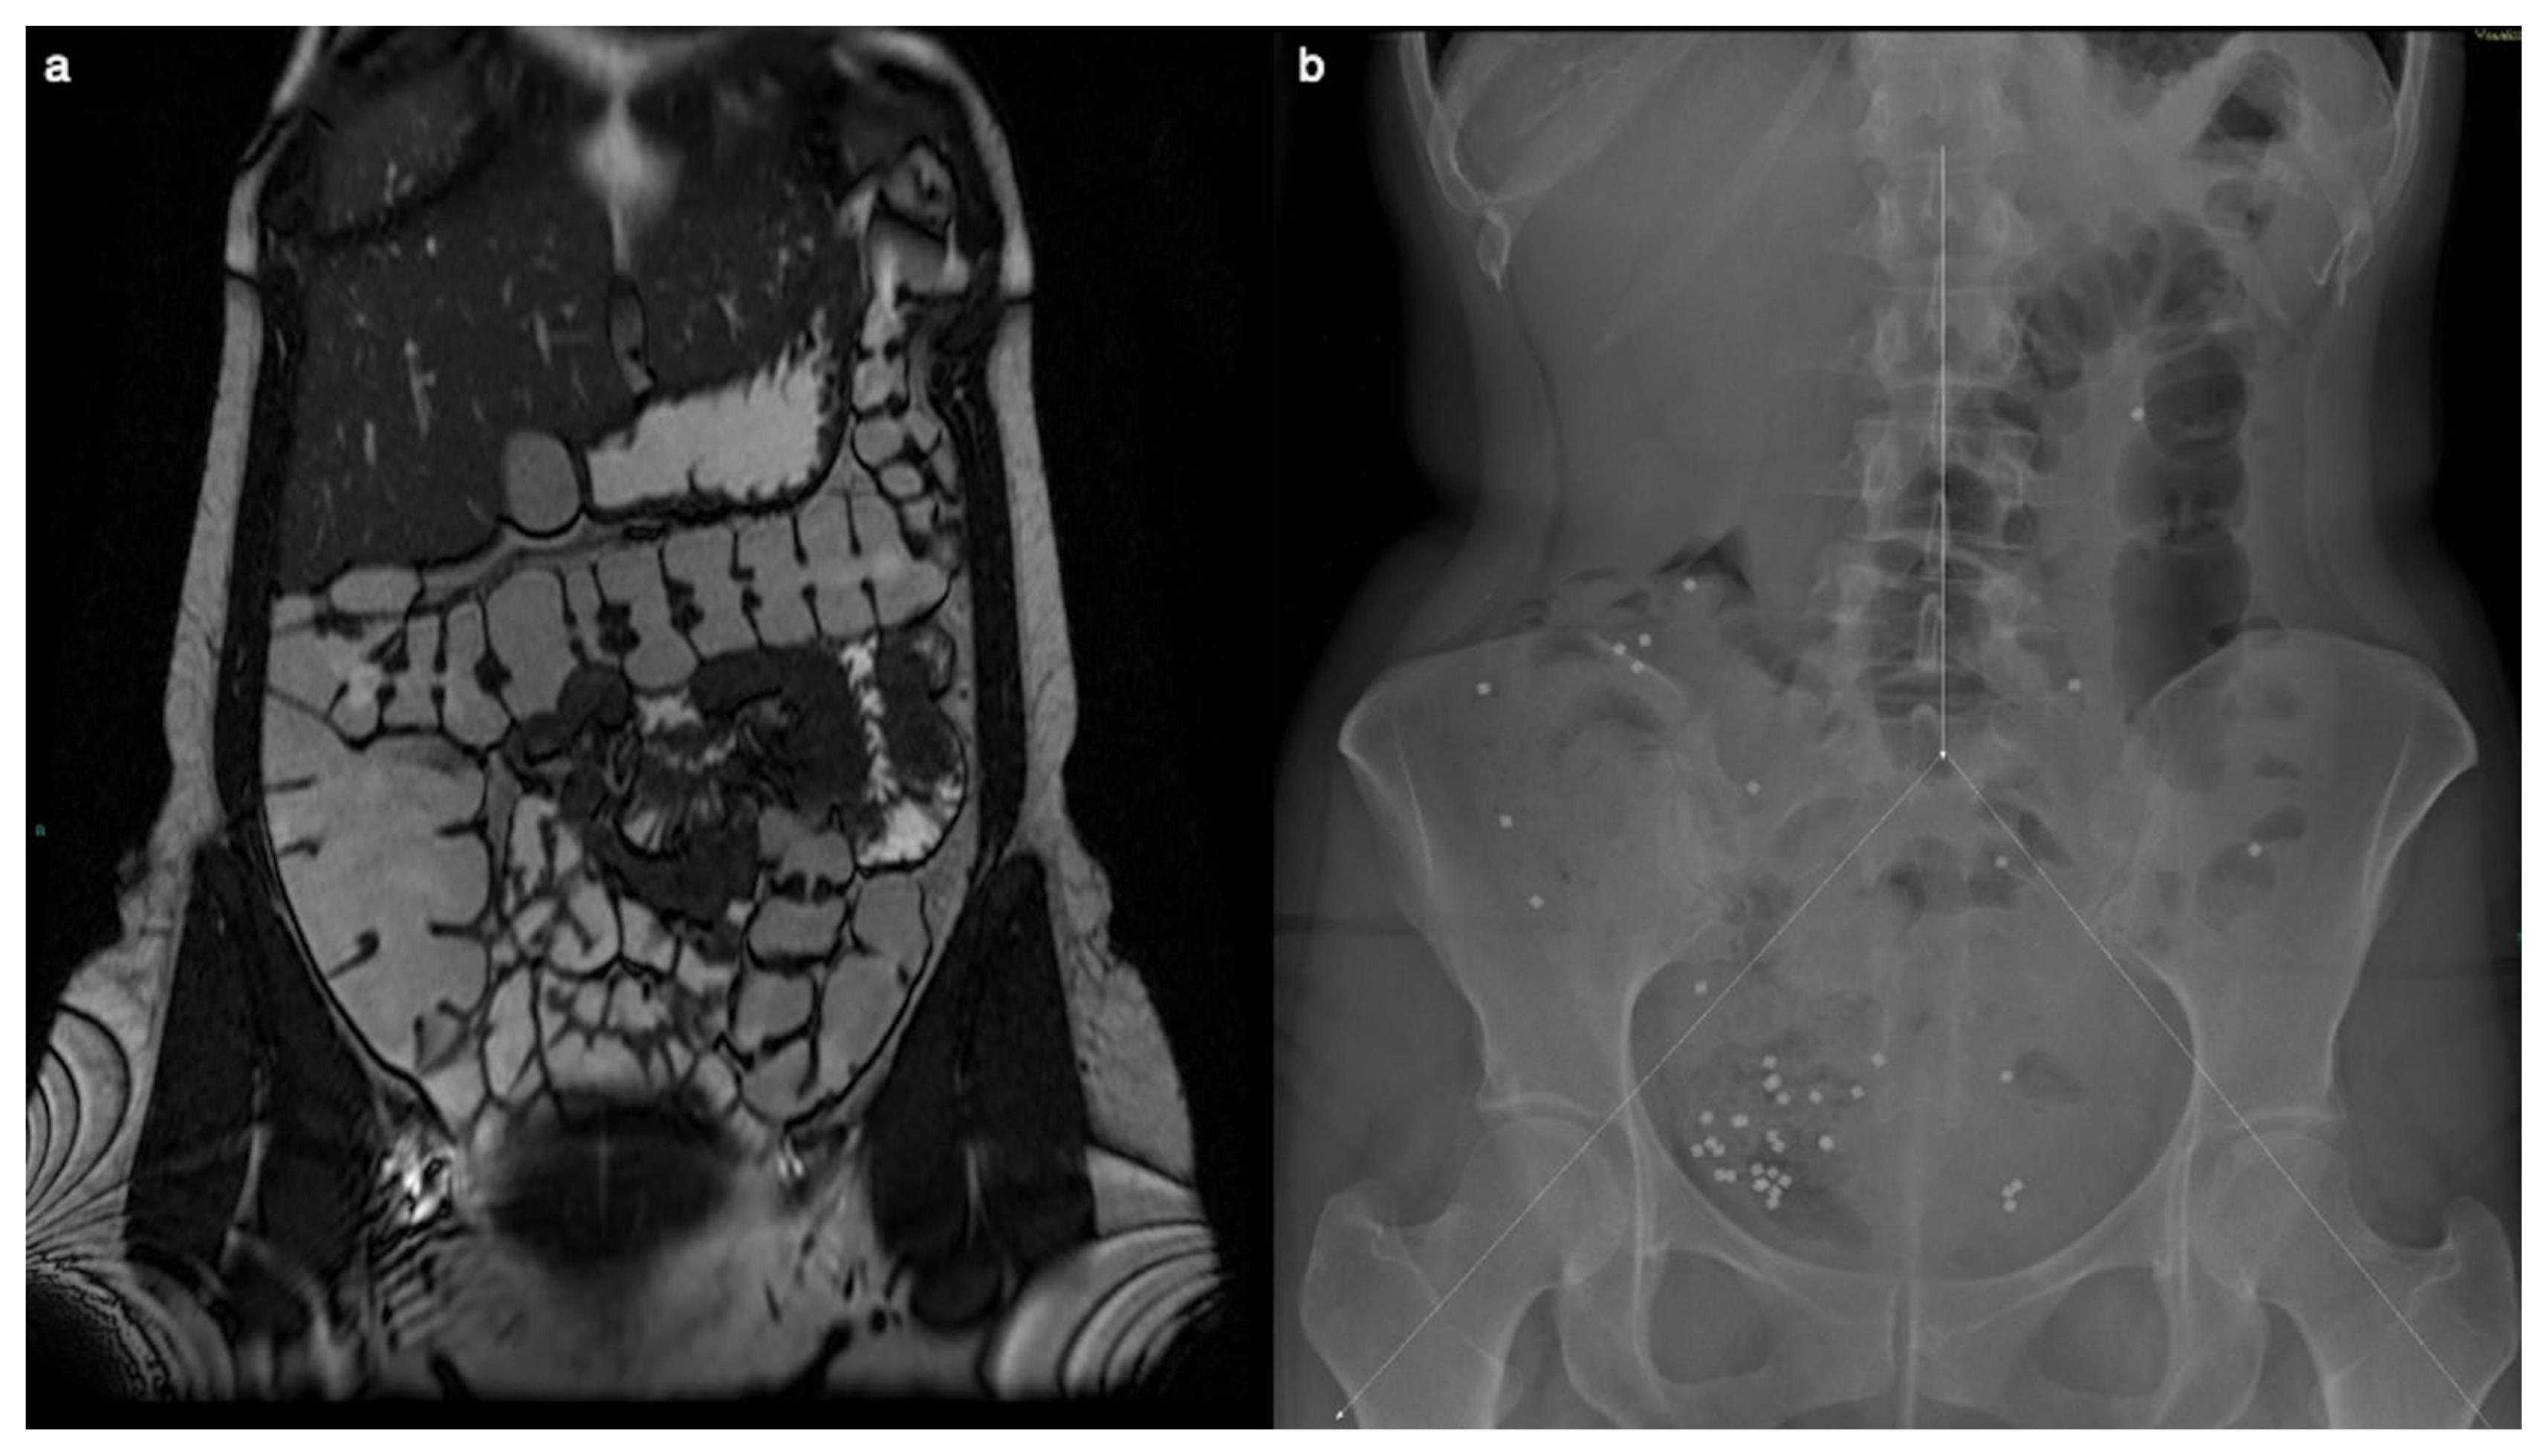

2. Case Presentation